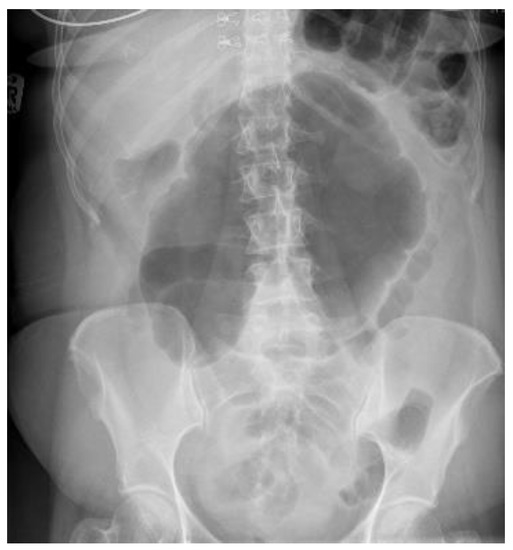

4.4.1. Conventional Radiography

- CT scan confirms diagnosis in >90%

- Typical Radiological Signs are described

- Representative X-ray and CT images presented

| Abdominal radiograph | 11 (68.75%) | Five patients had CT as the only imaging. |

| Non-specific bowel loops/SBO | 5 (46%) | |

| Classical single loop of large bowel | 6 (54%) | |